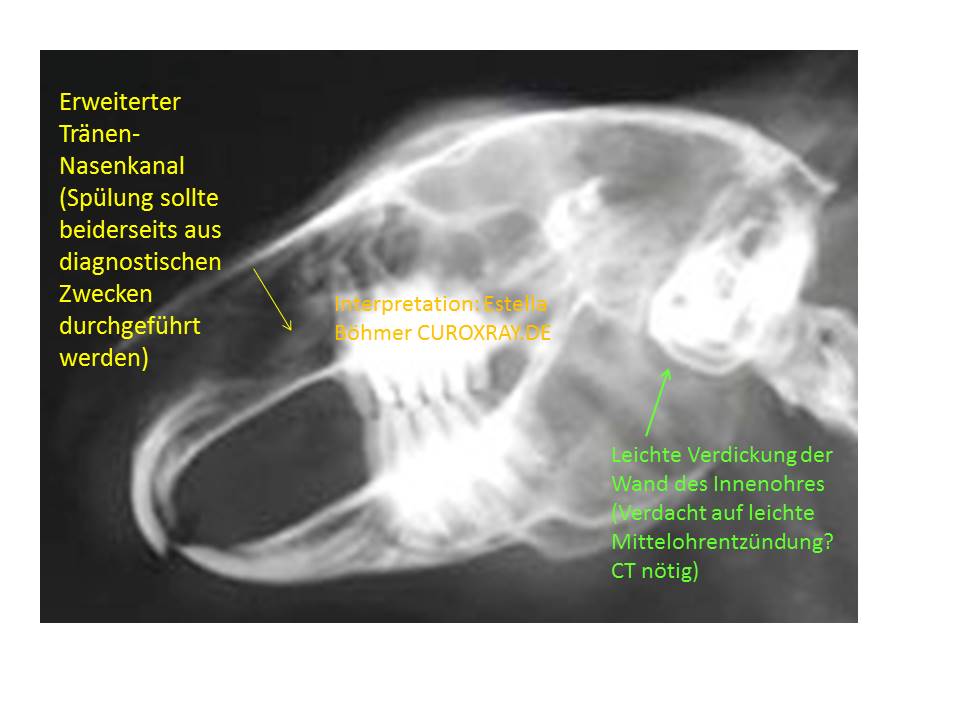

Diese Schräg-Aufnahme sowie die folgende latero-laterale Kopf-Aufnahme zeigen darüberhinaus, dass auch die Wand des Mittelohres (Bulla tympanica) leicht verdickt ist (grüner Pfeil). Normalerweise stellt sie sich als hauchdünne Linie dar. Das muss nichts bedeuten, könnte aber auf eine leichte Mittelohrentzündung hinweisen. Zumal in der Nase ein dichterer Bereich erkennbar ist, wo der Tränen-Nasenkanal eine Verdichtung aufweist.

Daher sollte der Tränen-Nasenkanal zumindest aus diagnostischen Gründen gespült werden. Das ist ohneNarkose möglich und gibt Auskunft über seine Durchgängigkeit.